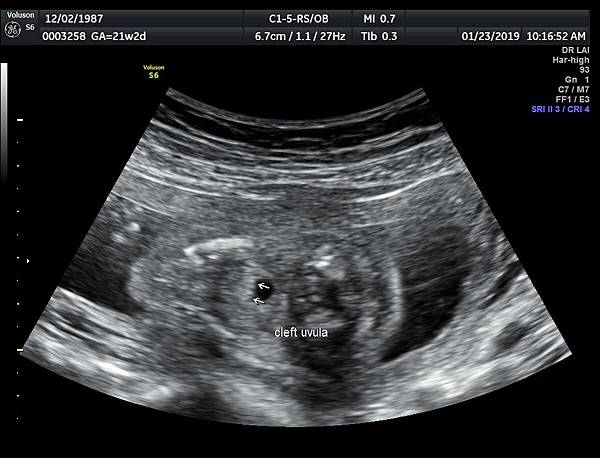

一個檢查如果要花很長的時間才能完成,這樣的檢查無法變成常規的篩檢方式,我已經在我的診所執行懸雍垂檢查一段時間,我檢查懸雍垂大約30 秒,前提是胎兒的臉最佳位置是側躺,其次是側躺偏向上,我的檢查步驟是上顎(含日後大門牙長出的位置)、舌頭、懸雍垂(= equal sign)(附圖1~8),如果超過60秒無法完成,只有兩個原因,一個是胎兒姿勢不適合或喉嚨羊水空間太小,這時候不要硬碰硬,只要先檢查其他部位,等待時機再回來即可,我的經驗是90%的cases都能順利完成這項檢查(肚皮厚的case真的是很難)。

有興趣的同業可以參考我的部落格備忘錄第119、120、127 及 236 這四篇,裡面有我做懸雍垂(uvula)的相關影像。